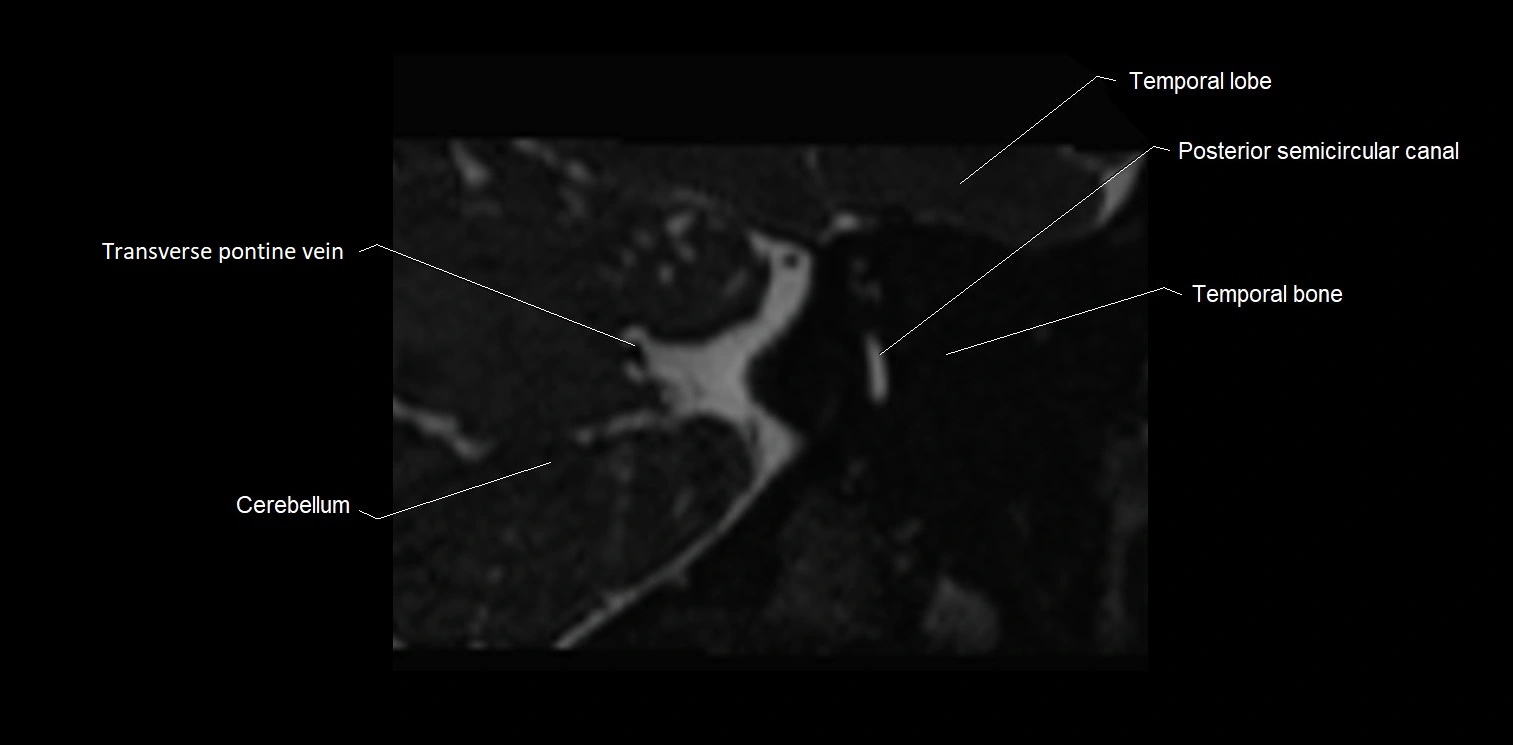

MRI Appearance

• The abducens nerve is a small, thin, linear structure

• Best visualized on high-resolution T2-weighted 3D MRI sequences (e.g., FIESTA or CISS)

• Seen as a hypointense (dark) line running from the brainstem at the pontomedullary junction, traversing the prepontine cistern, and entering Dorello’s canal under the petrosphenoidal ligament, then into the cavernous sinus, and finally the orbit

• May be challenging to visualize in standard MRI due to its small size

• Pathology may be inferred by absence, displacement, or enhancement of the nerve